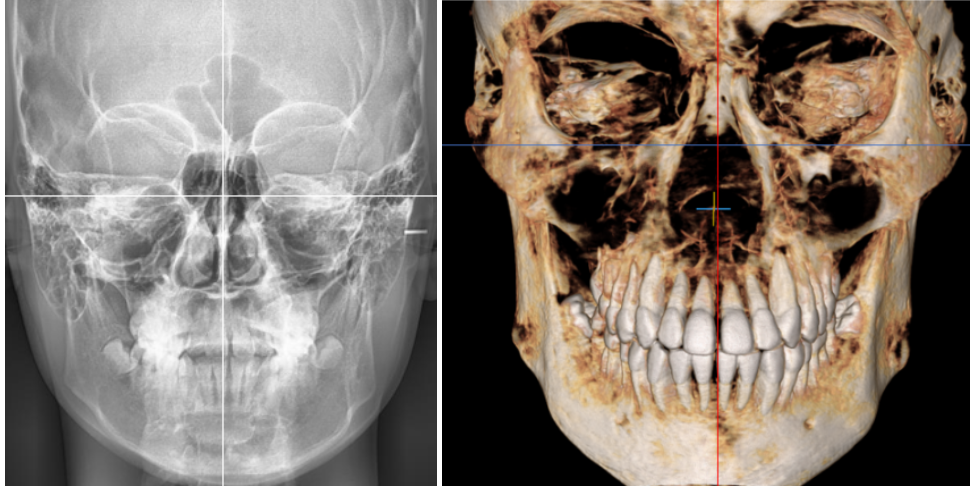

2024.01.08

안모를 봤을 때, 턱끝이 왼쪽으로 치우친

비대칭 양상이 관찰되었으나,(왼쪽)

눈확아래선을 기준으로 보면

골격의 비대칭은 심하지 않은 편입니다.(오른쪽)

어금니 교합이 정상인 점(1급 관계),

위턱과 아래턱이

조화로운 상태인 점(Skeletal class I)

등을 고려하여

비발치 교정을 결정했습니다.